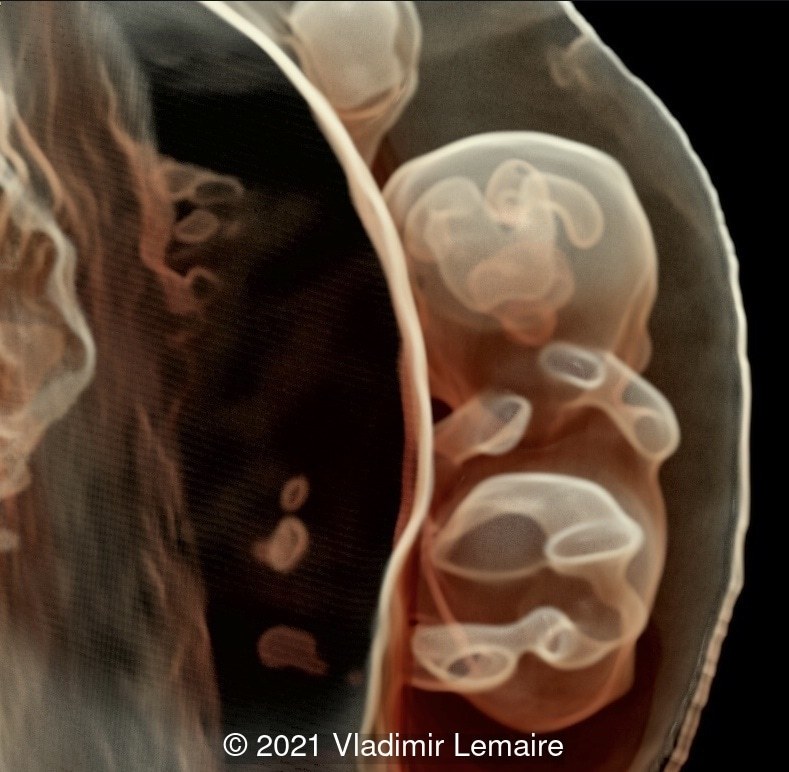

Three-dimensional ultrasound in multiplanar display of an embryo at 8weeks of gestation showing the brain vesicles.

Image 2 Three-dimensional ultrasound in multiplanar display of an embryo at 8weeks of gestation showing the brain vesicles.